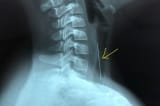

Đinh sắt hoen gỉ cong chữ U trong cổ bệnh nhi 8 tuổi

Một đoạn đinh sắt hình chữ U, cạnh dài nhất 2 cm, đầu sắc nhọn được gắp ra từ thực quản của bệnh nhi trong tình trạng đã hoen gỉ.